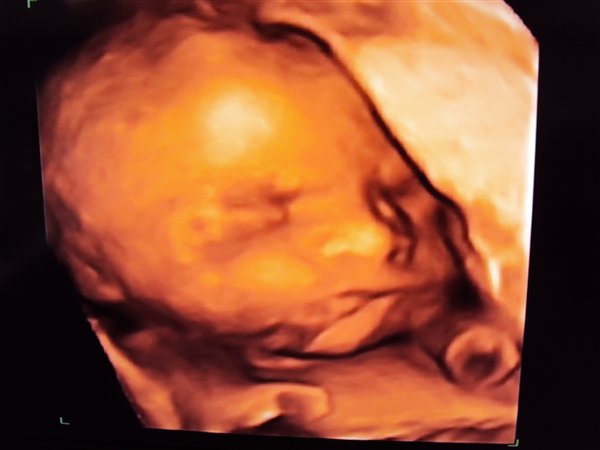

Vi fik afvide at han vejede 1 kg. her i uge 26 (25+4) Så han er en stor dreng. Han havde allerede fået deller og et tygt lag fedt på kroppen. Hun fortalte han formentlig ville være 4 kg. hvis han blev født til tiden, og ville bruge str. 56.

Sikke en dejlig dreng vi har der, og vi kan alle tydeligt se han har min mund. Hans tær er efter hans far - der var nemlig en af tærene der var lidt længer end de andre, hvilket min mand også har

Ellers kunne hun fortælle at næsen var meget lille og fin, og han allerede havde fået hår på hovedet.